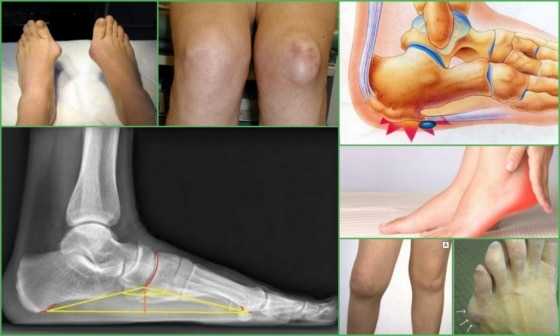

На фото экзостозы большого размера выглядят, как опухолевидные образования различного диаметра. Точная симптоматика зависит от локализации патологии. Рассмотрим проявления болезни при поражении нижних конечностей.

Стопа

На долю поражений стопы приходится 10-12% случаев патологии. Наросты обычно формируются в переднем и среднем отделах ступни, приводя к дискомфорту при ходьбе и хромоте. При экзостозе стопы чаще всего поражается плюсневая кость, которая по мере роста новообразования укорачивается и деформируется. В результате происходящих изменений соответствующий палец выглядит заметно короче остальных. Часто встречаются подногтевые экзостозы, приводящие к искривлению и отслоению ногтевых пластин.

В результате травмы сухожилий и связок развивается экзостоз пяточной кости. Формирующаяся опухоль может приобретать разнообразные формы и является серьезным косметическим дефектом. В половине случаев отмечается нарушение чувствительности заднего отдела стопы вследствие сдавливания нервных окончаний и сосудов. Болезнь часто сопровождается образованием отеков и припухлости вокруг экзостоза, болью и дискомфортом при ходьбе.

Постановка диагноза осуществляется на основе анализа жалоб пациента, пальпации пораженного участка тела и рентгенологического исследования. Рентген позволяет точно определить количество, размер, характер и локализацию наростов, а также дифференцировать их с другими патологиями костной ткани. На начальной стадии диагностика хрящевого экзостоза затруднена.

На рентгене видна только костная часть образования, а хрящевая прослойка не определяется. У детей толщина хряща может достигать 5-8 мм, поэтому истинный размер нароста будет отличаться в большую сторону.